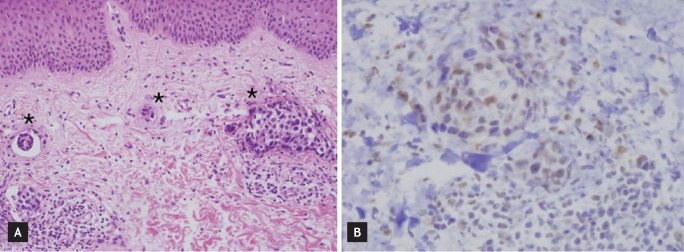

Two months later, the patient complained of multiple reddish nodules on her right chest wall, shoulder, and upper arm (Fig. 1A). Breast MRI showed skin enhancement of the right chest wall with an even thickness, and postoperative or postradiation skin changes were suspected (Fig. 1B). A skin biopsy was performed, and the slides were independently reviewed by two pathologists. ER and PR expression was scored using the semiquantitative Allred system, which takes into account the proportion of positive cells (graded from 0 to 5) and the staining intensity (graded from 0 to 3). Pathological examination showed an invasive ductal carcinoma with diffuse lymphatic invasion (Fig. 2A) that was positive for ER (intensity score, 3; proportion score, 3) and negative for PR and HER2 (Fig. 2B). A PET-CT scan showed heterogeneous hypermetabolic activity of the skin throughout the right chest wall and small hypermetabolic nodular lesions in the parasternal area, but there were no other visceral metastases. The patient, who was premenopausal, was administered hormone therapy comprised of a gonadotropin-releasing hormone agonist and tamoxifen (20 mg daily). After three cycles of hormone therapy, follow-up breast MRI showed stable disease for the skin enhancement of the right chest wall.

Figure 2

(A) Metastatic carcinoma cells with diffuse lymphatic invasion (asterisks) in the dermis were observed (H&E, ×200). (B) Positive immunohistochemical staining for the estrogen receptor was detected ( ×400).